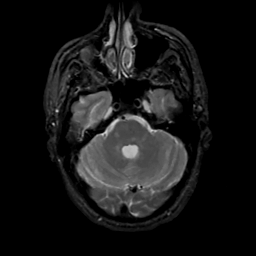

MR Study #15, June 9, 1991 -- Slice #13

[Home][Help][Clinical][Tour 1][Tour 2] Slice 13